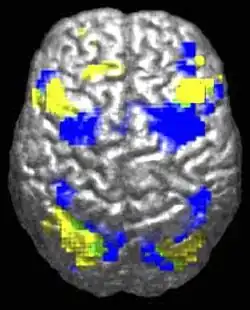

Neuroanatomical studies support that autism may involve abnormal neuronal growth and pruning, leading to brain enlargement in some areas and reduction in others.[13] Functional neuroimaging studies show reduced activation in somatosensory cortices during theory of mind tasks in autistic individuals and highlight potential imbalances in neurotransmitters like glutamate and Γ-aminobutyric acid that may underlie autism's behavioral manifestations.[14]

The underconnectivity theory of autism posits that autistic people tend to have fewer high-level neural connections and less global synchronization, along with an excess of low-level processes.[31] Functional connectivity studies have found both hypo- and hyperconnectivity in brains of autistic people.[32] Hypoconnectivity is commonly observed for interhemispheric (e.g. lower neuron density in corpus callosum)[33] and cortico-cortical functional connectivity.[34] Some studies have found local overconnectivity in the cerebral cortex and weak functional connections between the frontal lobe and the rest of the cortex.[35] Abnormal default mode network (task-negative) connectivity is often observed. Toggling between task-negative network activation and task-positive network activation (consisting of the dorsal attention network and salience network) may be less efficient, possibly reflecting a disturbance of self-referential thought.[36] Such patterns of low function and aberrant activation in the brain may depend on whether the brain is performing social or nonsocial tasks.[37]

Brains of autistic individuals have been observed to have abnormal connectivity and the degree of these abnormalities directly correlates with the severity of autism. Following are some observed abnormal connectivity patterns in autistic individuals:[33][18]

- Prominent abnormal connectivity in the frontal and occipital regions. In autistic individuals low connectivity in the frontal cortex was observed from infancy through adulthood. This is in contrast to long-range connectivity which is high in infancy and low in adulthood in ASD.[33] Abnormal neural organization is also observed in the Broca's area which is important for speech production.[18]